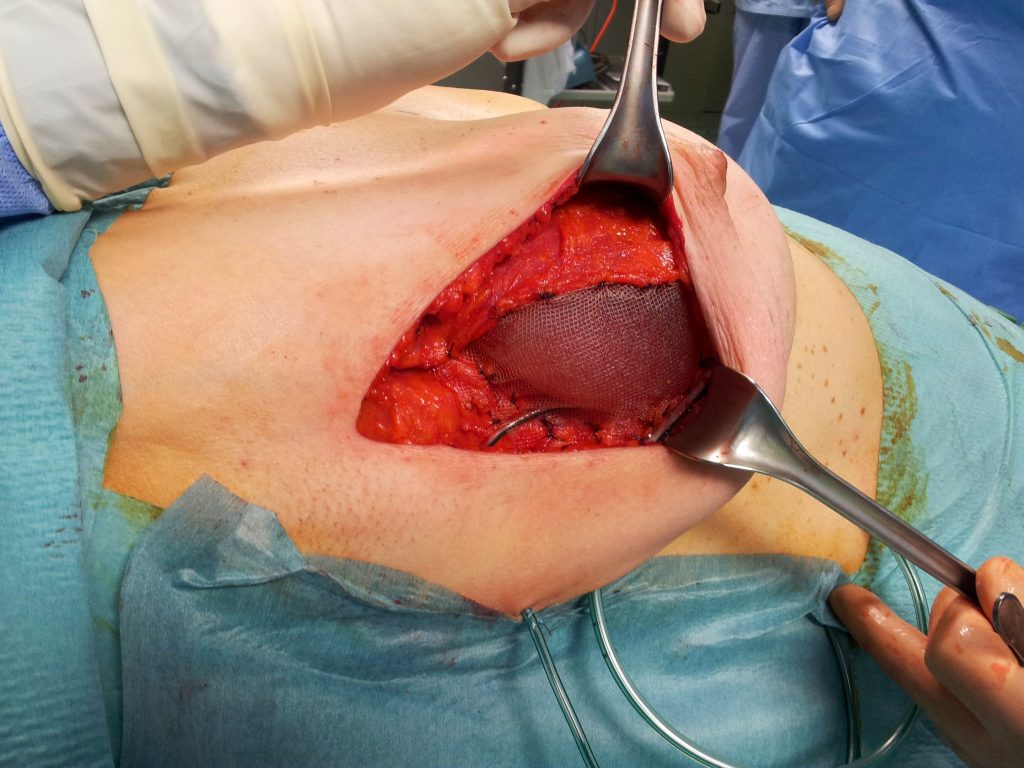

Ricostruzione mammaria con impiego di rete in un tempo unico

Non in tutte le mastectomie, però, si può adottare questa tecnica. Oltre alla raccomandazione che l’intervento venga eseguito solo da chirurghi esperti sia in campo oncologico sia in quello estetico, per evitare rischi occorre prima di tutto che il tumore si trovi ad almeno 2 cm dal complesso areola-capezzolo. Per la ricostruzione del seno dopo interventi demolitivi è possibile ricorrere a diverse tecniche, a volte anche combinate tra loro. La più innovativa è rappresentata da una membrana sottile, chiamata mesh, simile a quelle usate nell’ernia, che, insieme all’utilizzo di una protesi mammaria, consente una ricostruzione immediata anche nel caso di mammella di medie dimensioni.

la rete costituisce la parete laterale della tasca muscolare dove è posizionata la protesi